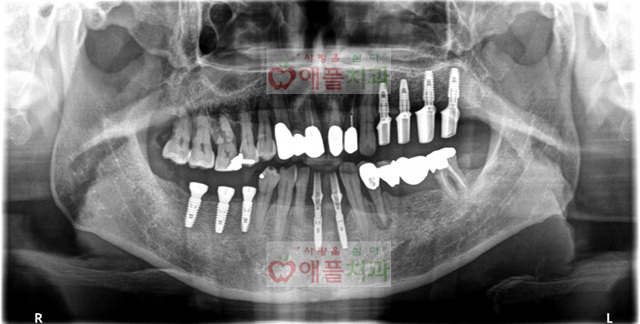

<처음 내원시>

582927201c628.jpg

컴퓨터분석으로 하루만에 9개의 임플란트 시술을 받으셨습니다. 특히 아랫니 앞은 발치하면서 즉시 임플란트 시술하면서 당일 보철도 제작해드렸습니다.

직업때문에 치과 내원을 자주 못하신 분이셨는데, 당일 컴퓨터분석을 통해서 시술 받으시면서 심미적 만족을 드리면서 내원 횟수를 확~줄였습니다.